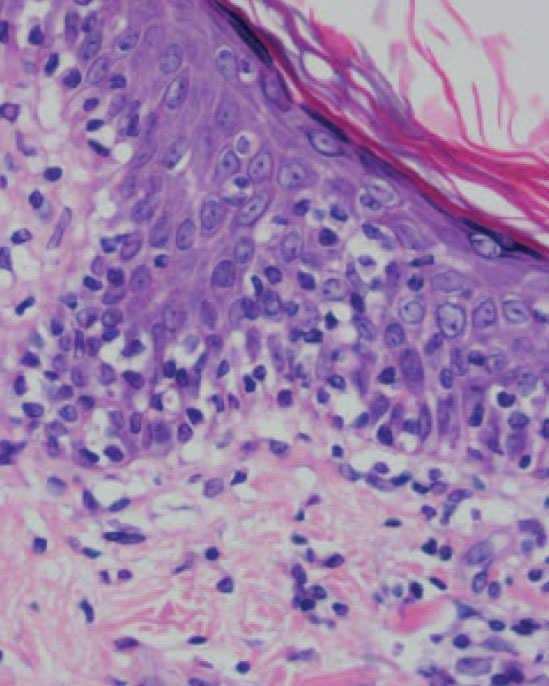

Se practicaron varias biopsias cutáneas, algunas de ellas sin alteraciones significativas. En otras se observó (figs. 4-6) una epidermis con hiperqueratosis y paraqueratosis focal, elongación de las crestas interpapilares y focos de degeneración hidrópica basal, con algún cuerpo apoptótico aislado. En dermis superficial y media existía un infiltrado linfocitario perivascular. Llamaba la atención la exocitosis de linfocitos atípicos intraepidérmicos, alguno de ellos con halo claro perinuclear y en alguna zona incluso iniciando la formación de microabscesos de Pautrier.

Fig. 4.—Paraqueratosis focal, elongación de crestas interpapilares, focos de degeneración hidrópica basal. (Hematoxilina-eosina, ×40.)

Como ocurrió con nuestro paciente, el estudio histopatológico en los estadios iniciales de la enfermedad puede ser muy inespecífico, lo que motiva además el retraso diagnóstico. En las fases más avanzadas revela la presencia de epidermotropismo de linfocitos anómalos, que a veces constituyen microabscesos de 5,6,8,11-23. En contraste con la micosis fungoide clásica, en esta variante parece que se observa un epidermotropismo más llamativo en contraste con un infiltrado linfocitario moderado en la dermis24.